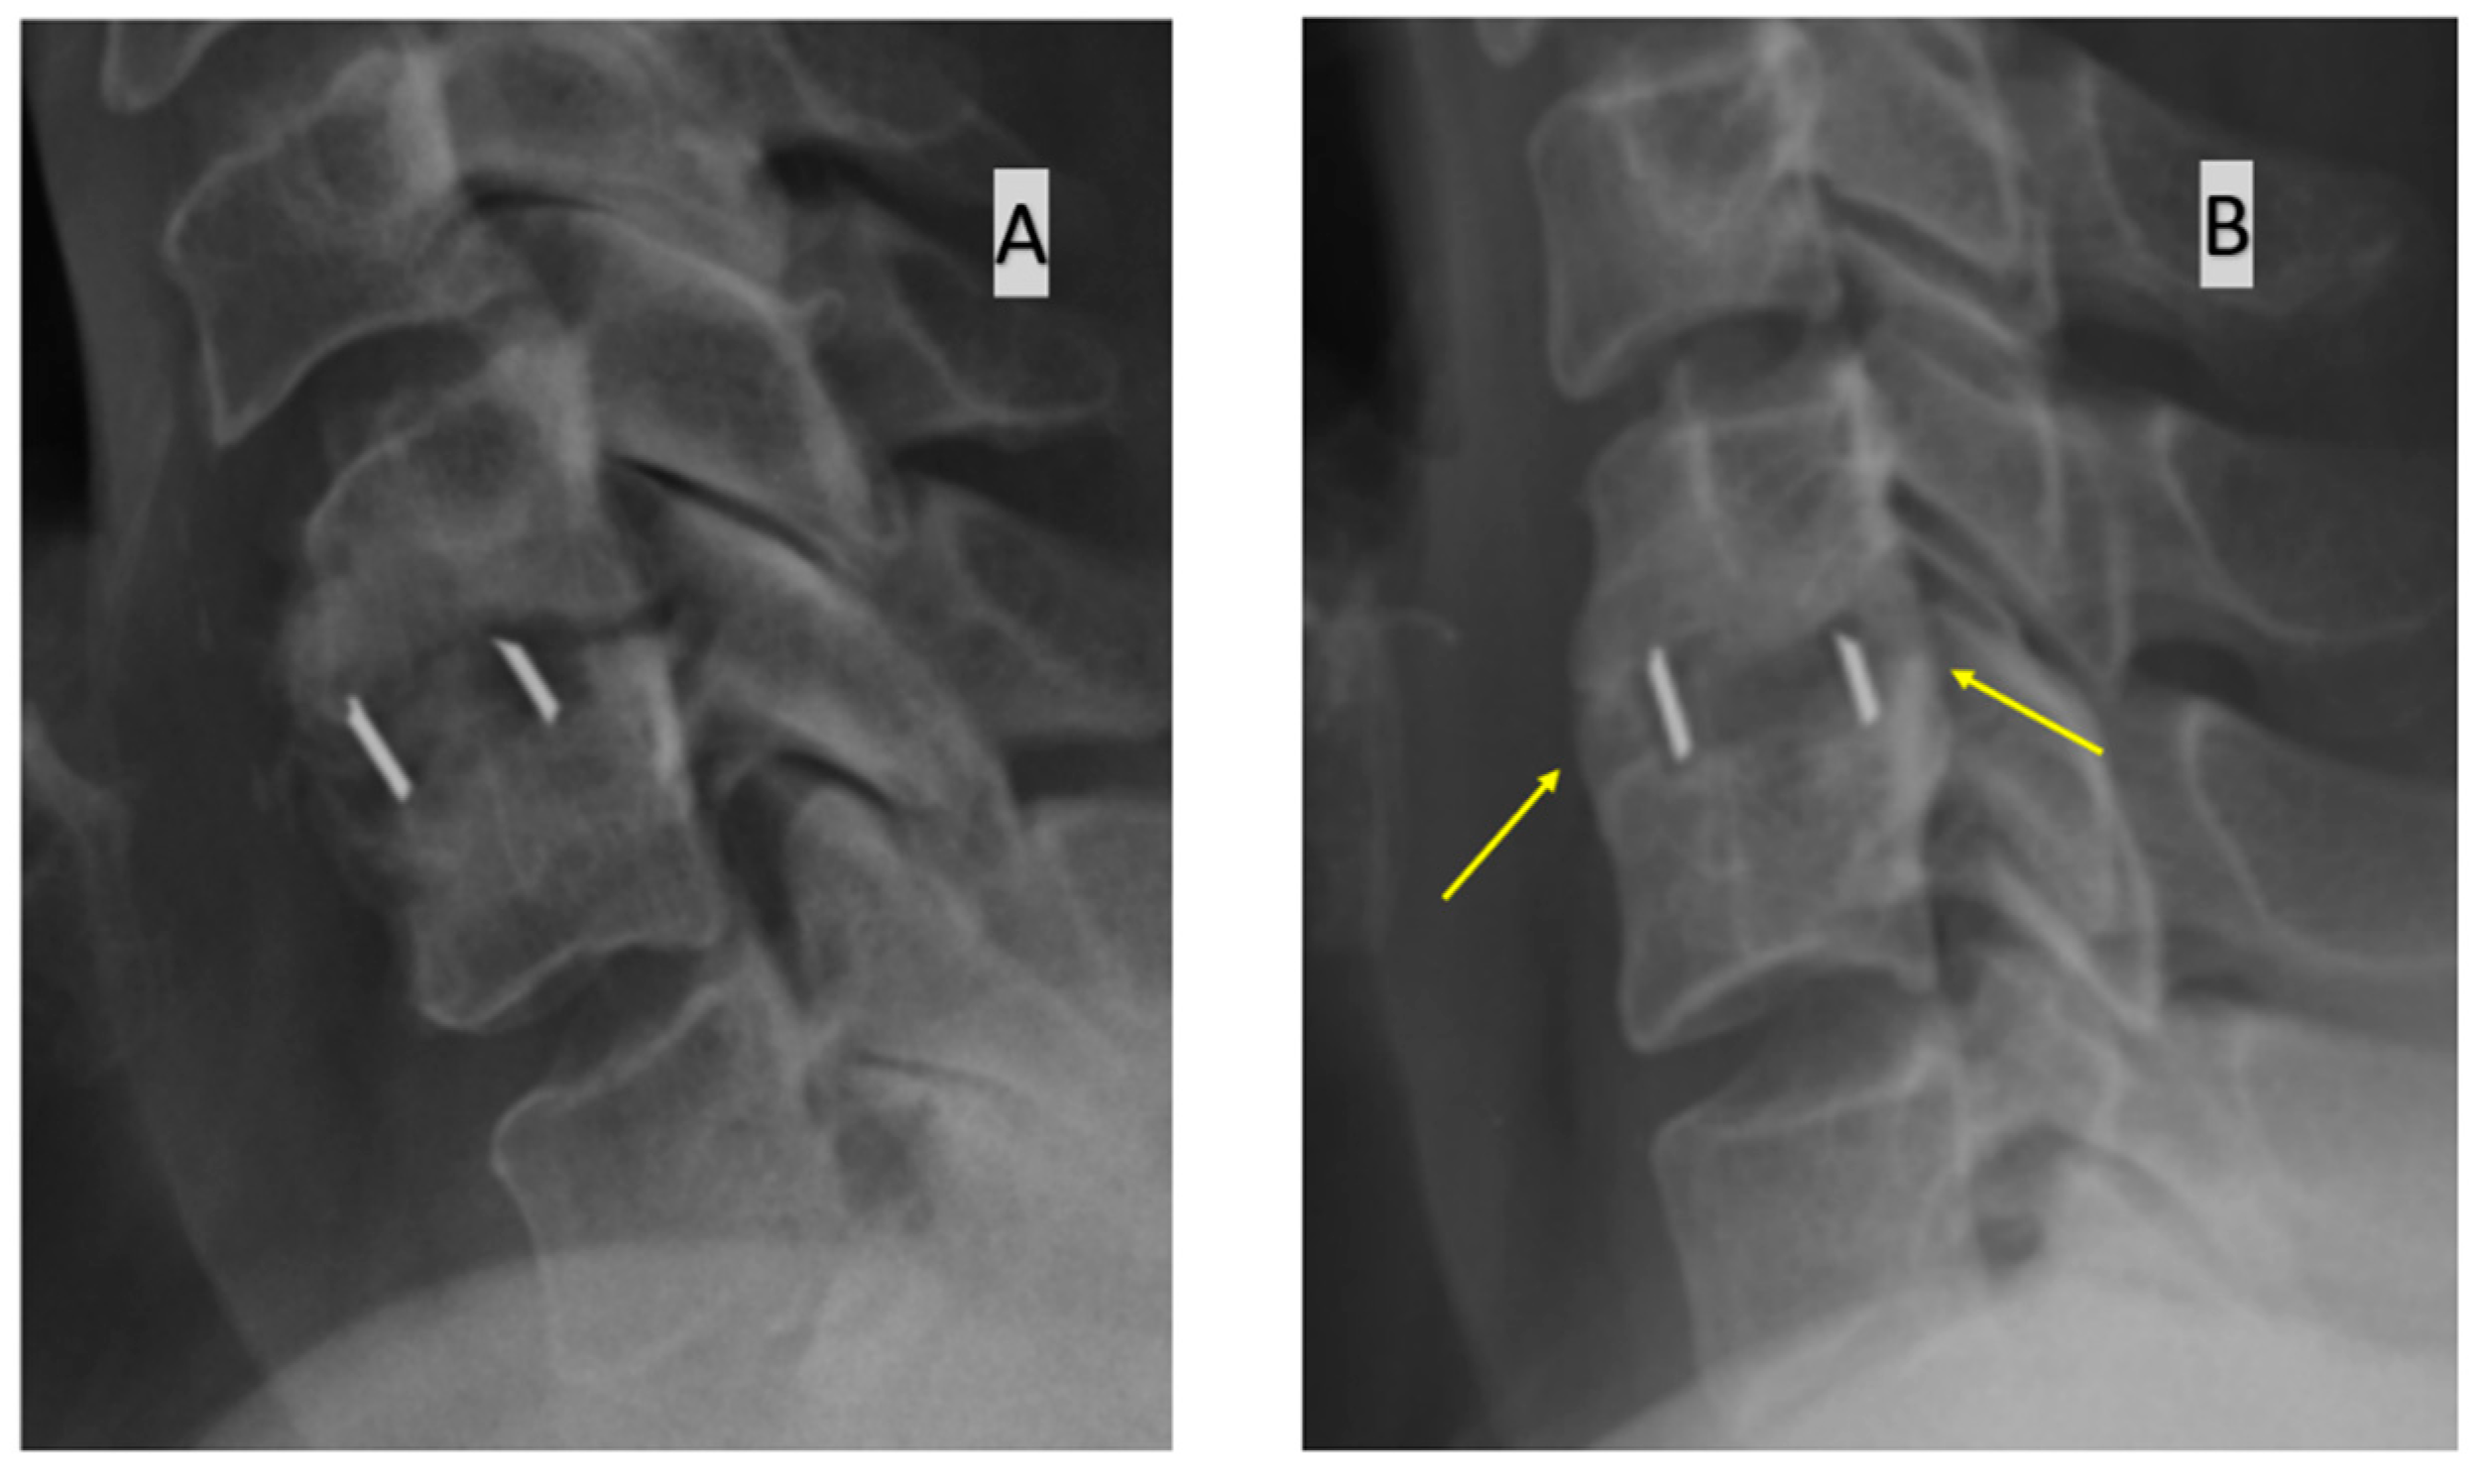

- bone bridging visible on the anterior and/or posterior edge of the operated disc space in a lateral radiograph. Fusion is diagnosed when bone bridging is visible, and if it is not visible, a pseudoarthrosis is diagnosed.

| Functional radiographs | Mobility of implants against vertebral bodies on functional radiographs | No mobility | No mobility | Visible mobility |

| Computed tomography images | Continuity of bone tissue immediately anterior, posterior, medial and lateral to implant on CT scan | Visible bone tissue continuity | No continuity of bone tissue | No continuity of bone tissue |